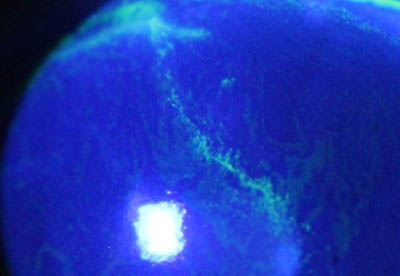

Formación de lineas epiteliales elevadas que pueden dar la imagen de Seudodendrítas

Formación de lineas epiteliales elevadas que pueden dar la imagen de Seudodendrítas + Perineuritis

El cuadro clínico inicial progresa, aparecen infiltrados estromales anteriores focales o difusos, edema circunscrito y a veces perineuritis

En su evolución se observará aumento del edema, aparición de un anillo inmunológico (Wessely), agrandamiento y coalescencia de los infiltrados que progresan hacia la formación de un absceso, queratolisis superficial, adelgazamiento y perforación corneal.

La vascularización y el hipopion son poco frecuentes en los estadios tempranos de la queratitis. Con el tiempo, en los estados avanzados de invasión estromal, aparecen vasos estromales